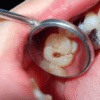

For anyone that has sensitive teeth, they know how difficult it can be to consume hot drinks like coffee or tea, eat frozen foods like popsicles or ice cream, clench your teeth together, or even breathe in cool air. If the pain is lingering or you have been experiencing severe discomfort for weeks, you need to take the necessary steps to reduce the pain associated with sensitive teeth. Here are a few ways to reduce and prevent sensitive teeth irritation: